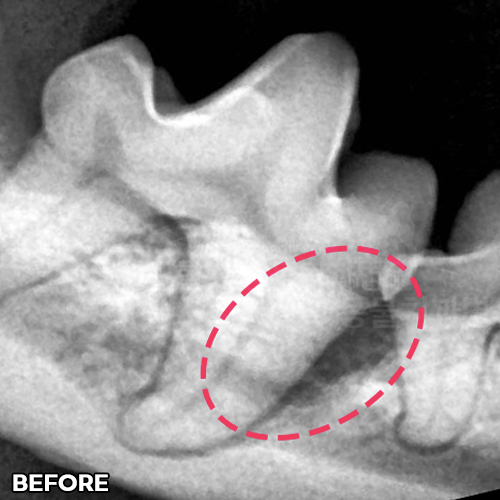

[사라진 강아지 턱떨림 / 재생된 턱뼈]